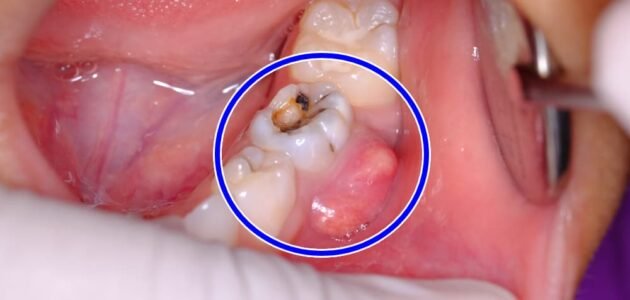

ما هو خراج الاسنان وعلاجه، يعرف خراج الأسنان بأنه عبارة عن صديد يخرج من مناطق قريبة من السن بسبب الاصابة بالعدوى البكتيرية، وينقسم الخراج الى نوعين هما : خراج دواعم السن و خراج قمي، فخراج دواعم السن عادة ما يتكون في اللثة بالقرب من جذر السن، أما الخراج القممي فيتكون في نهاية الجذر، ويحدث بسبب معالجة سابقة للأسنان، او عدم حدوث معالجة لتجويف الأسنان، فتصاب اللثة بالتهيج والتورم مما يؤدي الى ظهور خراج في طرف الجذر .

يجب على الشخص زيارة الطبيب فورا في حال ظهور أعراض تشير الى الاصابة بخراج في الأسنان، وذلك لتفادي المضاعفات التي تصبح خطيرة بمرور الوقت، ولا بد من زيارة الطبيب بأسرع وقت ممكن عند تورم الوجه والشعو بالحمى، خاصة اذا كان الشخص يعاني في الأساس من صعوبة في التنفس، يحدث الخراج بسبب اصابة لب الأسنان بعدوى بكتيرية، حيث تدخل هذه البكتيريا من خلال وجود تكسر في السن او اصابة السن بالتسوس.